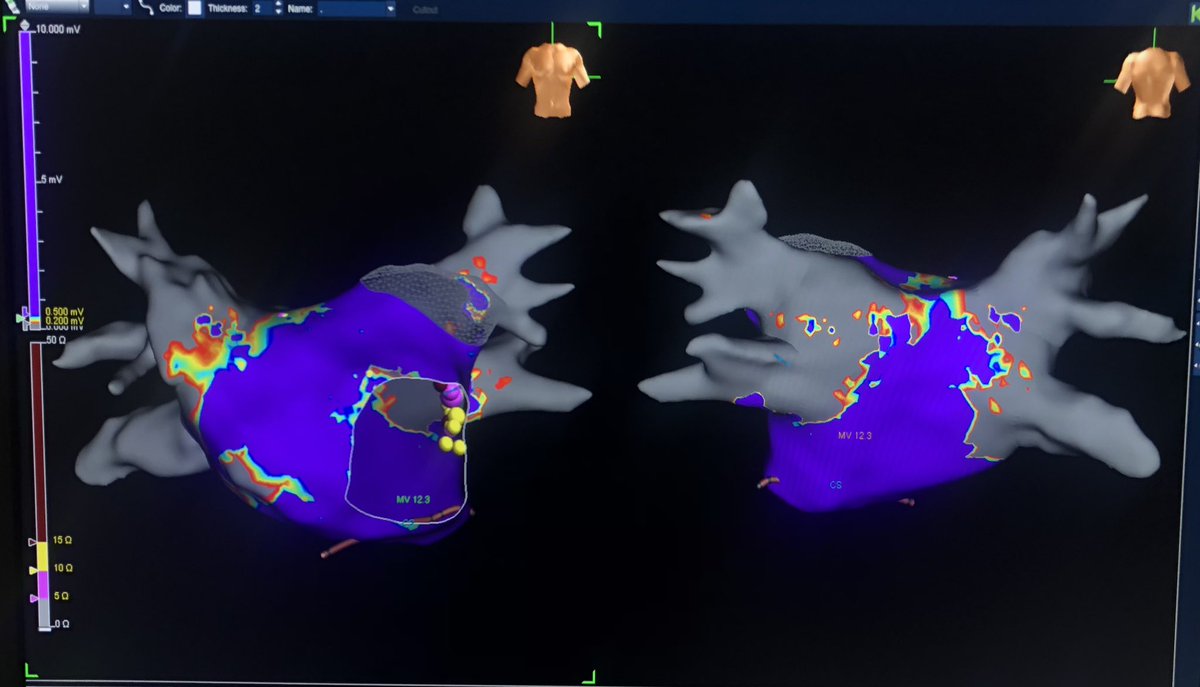

Atrial late activation mapping in a patient with recurrence after PVI + anterior mitral line. Latest activated zone with fragmented signals during sinus rhythm predicts critical isthmus of roof- dependent macro-reentry & successful termination site. #EPeeps